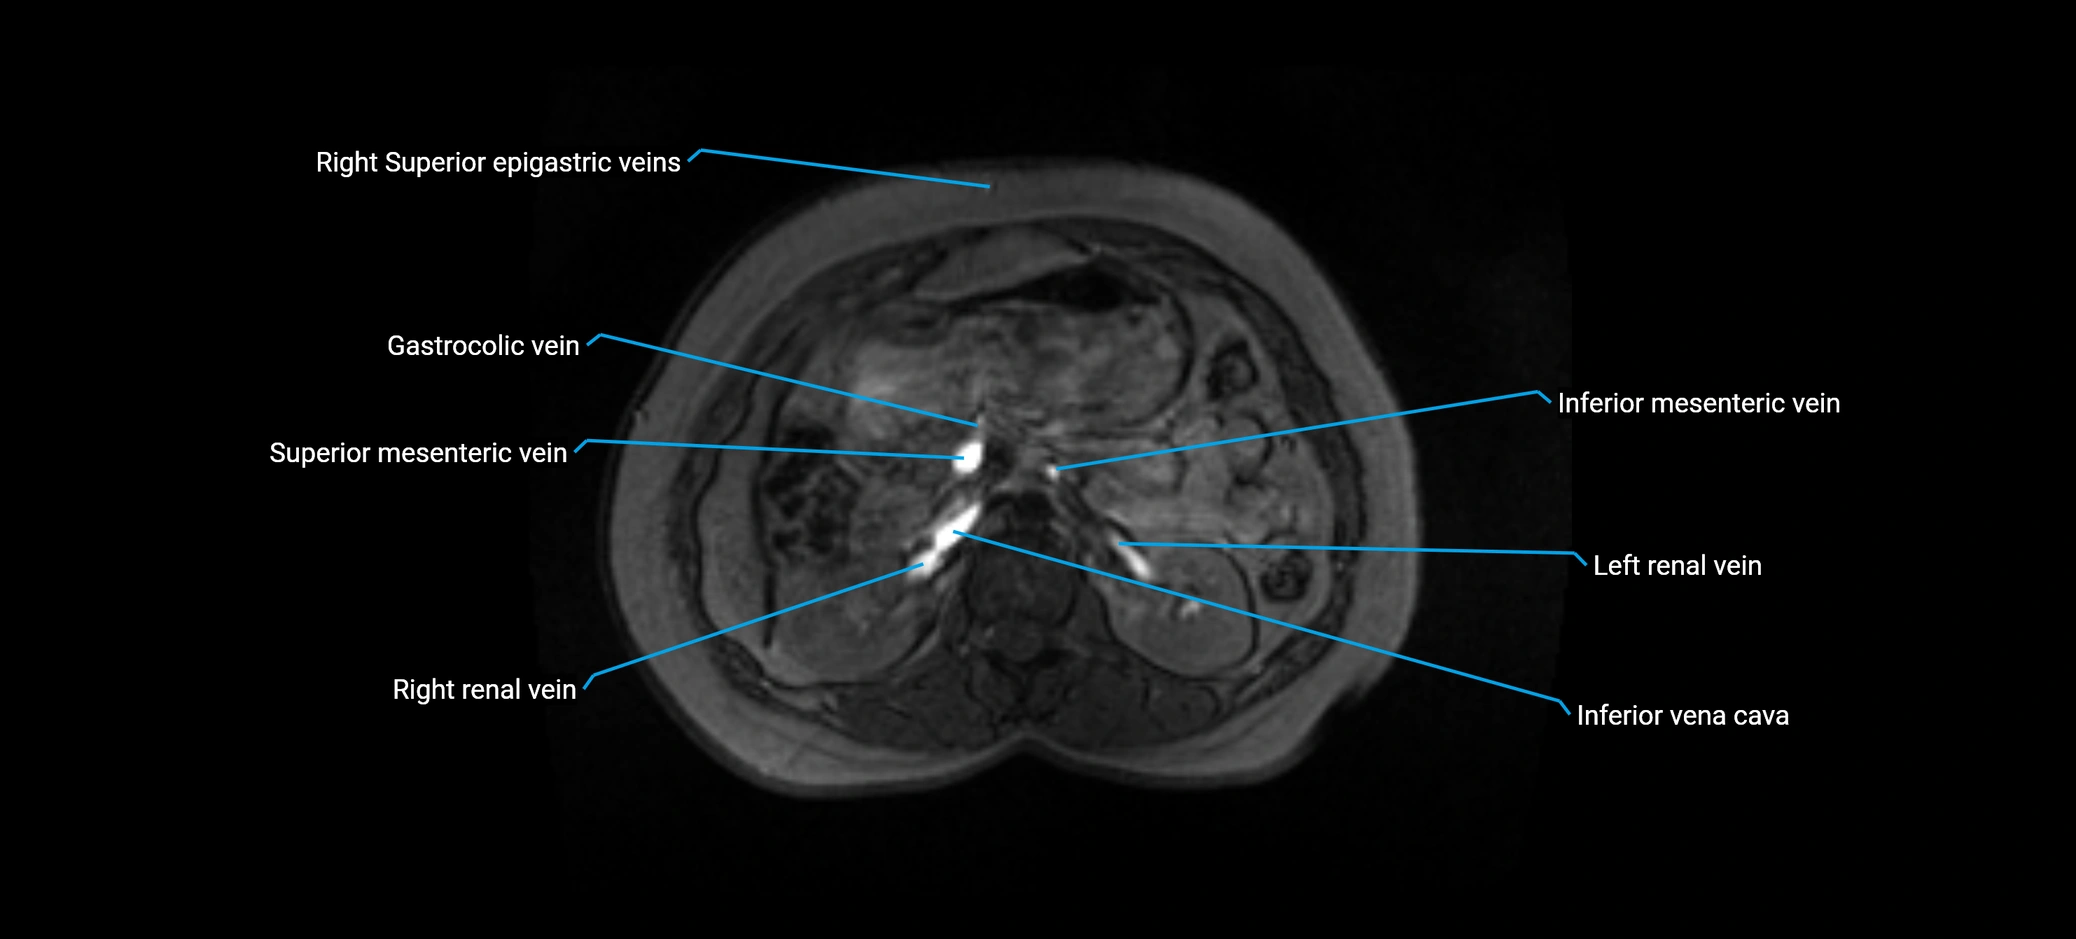

MRI image

image